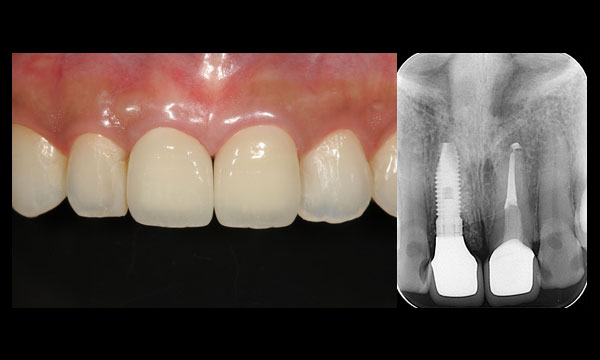

症例1

術前

前歯が根の途中から折れてしまいました。

術後

インプラントを使って、審美、機能回復しました。